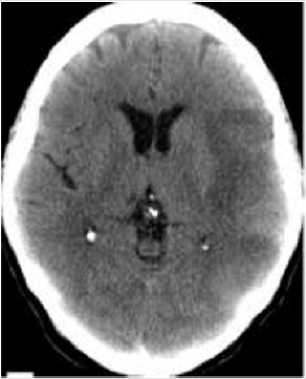

Vascular Dementia is diagnosed in this patient and medical treatment is started. The rTMS protocol, the Dementia protocol and the cerebrovascular disease of the Actipulse team were started (Figure 2). Evaluation of the patient at 2 months, we see a patient who integrates into a family environment, performs household chores. Cooperating and socializing with their environment. Mini mental test 22 points.

Figure 2: CT scan of the simple skull of patient 2. A hypodense image is observed in relation to left-sided cerebral artery ischemic CVD, which affects the left parietal fronto region.